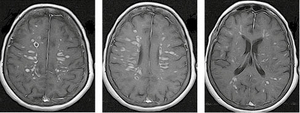

На рисунку 1 представлено МРТ-зображення головного мозку пацієнта з ГРЕМ у режимах Т2, Т2/Flair та Т1 із внутрішньовенним контрастуванням. Зокрема, візуалізуються двобічні вогнища округлої та овоїдної форми, гіперінтенсивні в режимах Т2 та Т2/Flair, які в більшості випадків накопичують контраст.

/images/nn257-1622023r1_.jpg)